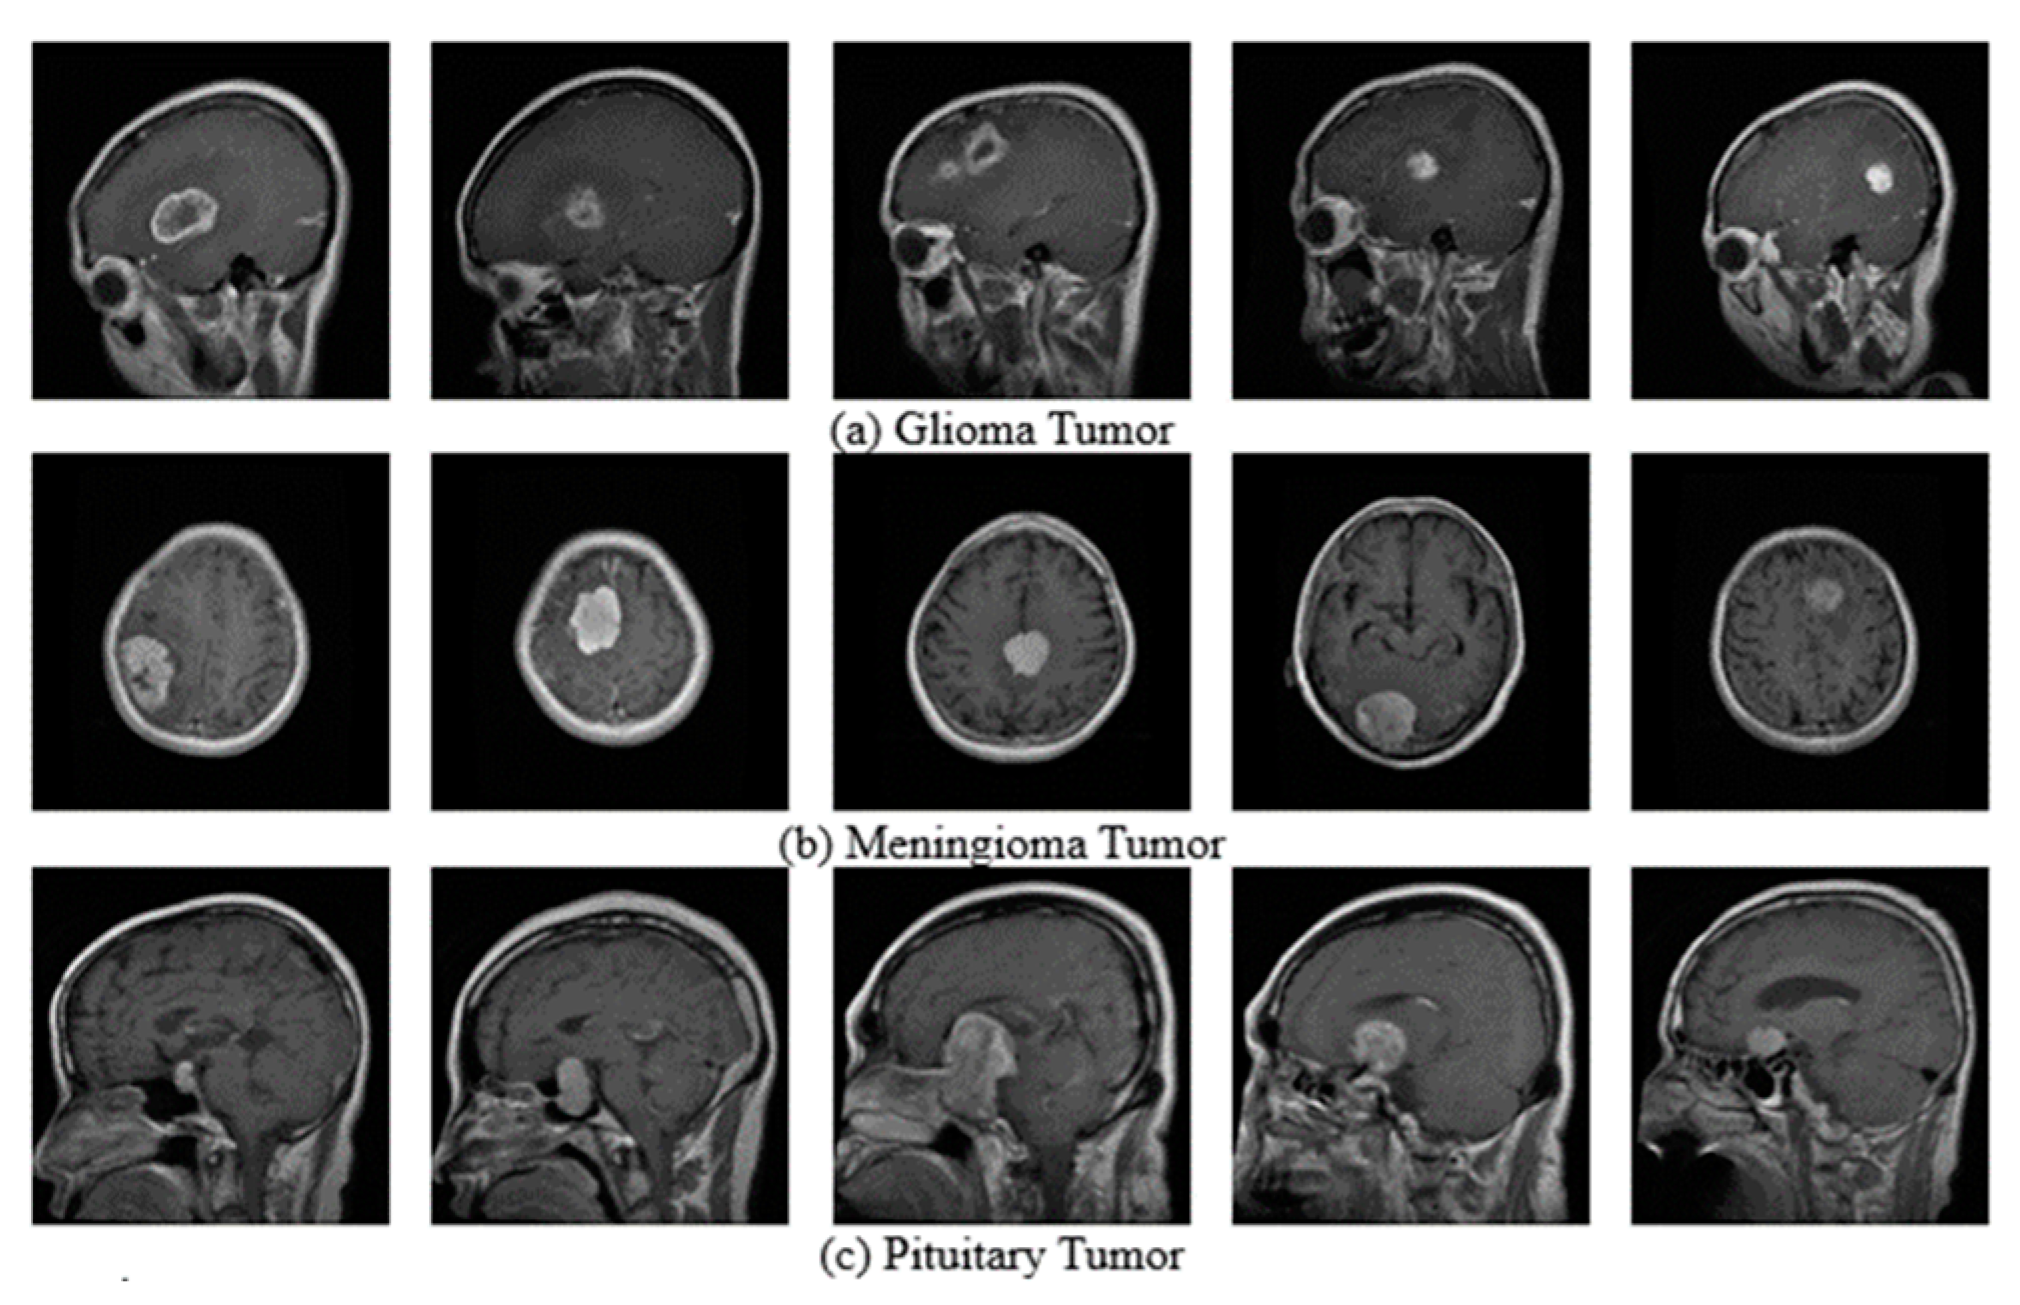

3.1. Datasets

- Sartaj, B. Brain Tumor Classification (MRI). Kaggle. Available online: https://www.kaggle.com/datasets/sartajbhuvaji/brain-tumor-classification-mri (accessed on 6 June 2023).

- Nickparvar, M. Brain Tumor MRI Dataset. Available online: https://www.kaggle.com/datasets/masoudnickparvar/brain-tumor-mri-dataset (accessed on 28 June 2023).